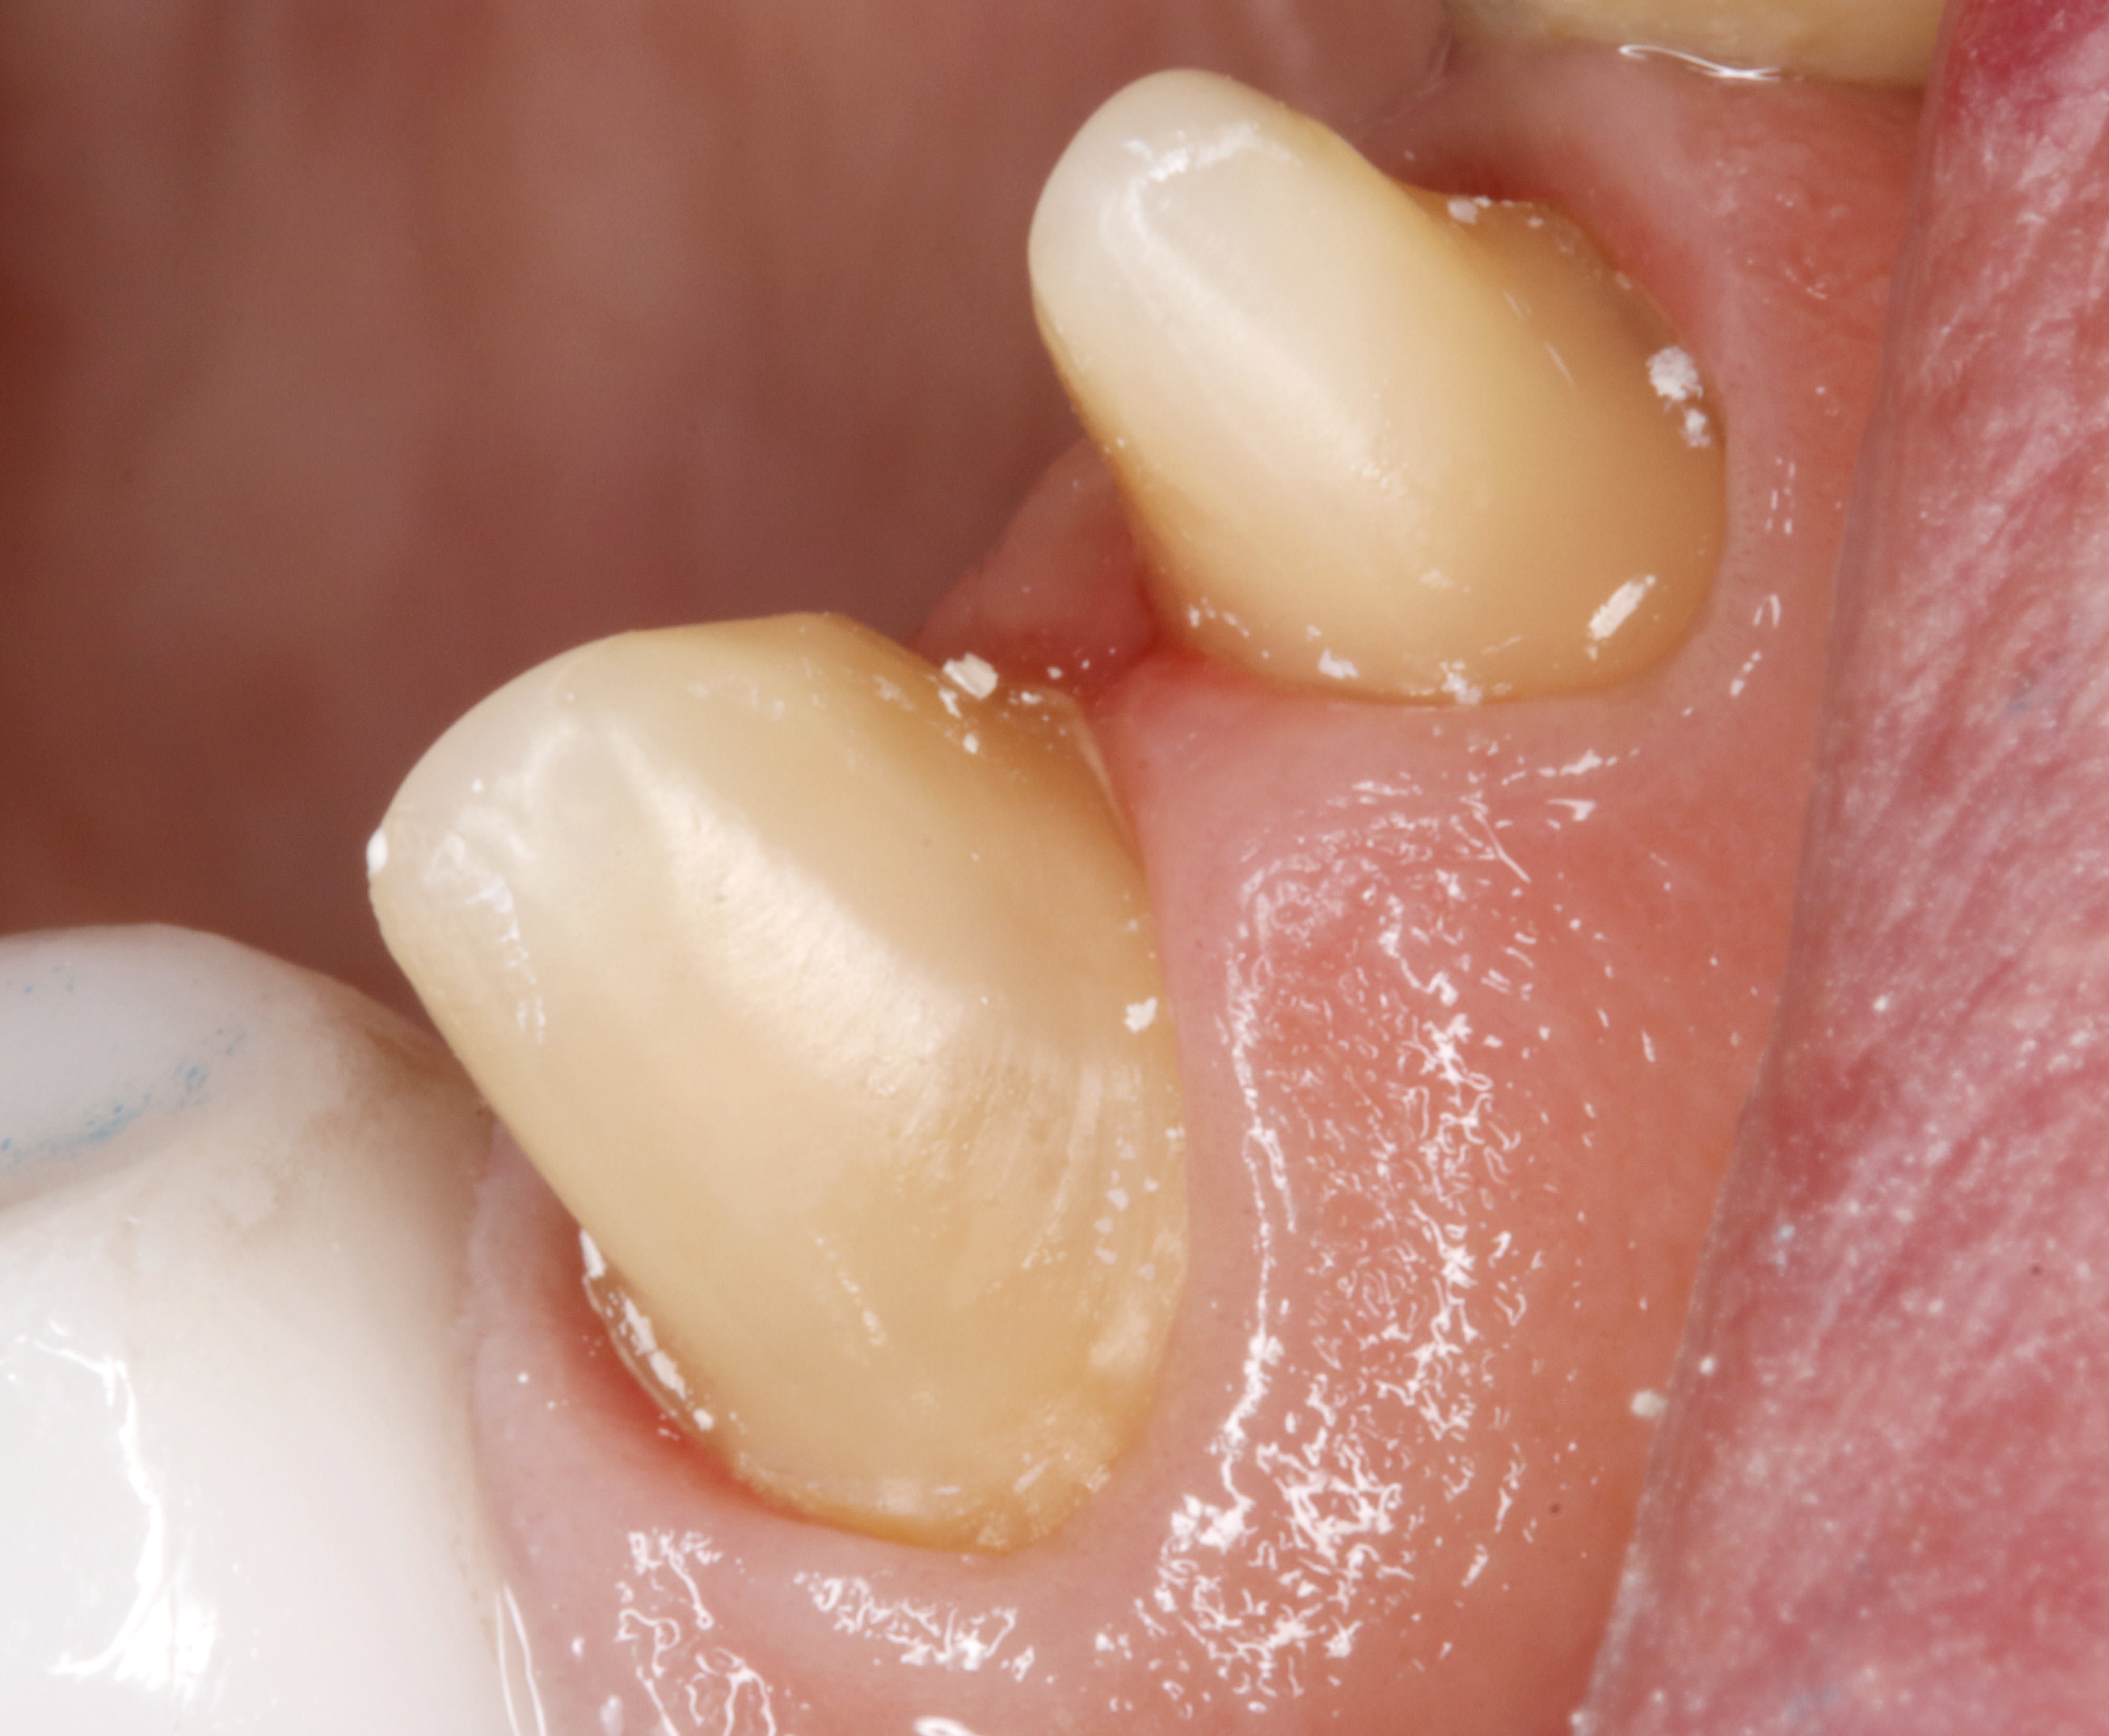

suite du chausse pied .

la séance d'après , lorsque tu déposes le prov ,le ciment prov reste sur le prov .

le sulcus ,qui n'avait pas saigné , est comme tu l'avais laissé , et il n'y a pas de surprise à l'essayage de la couronne .

avec cette stabilité tu en as pour des années ,je pense .

retour à l'envoyeur pour évaser un poil l'embrasure .